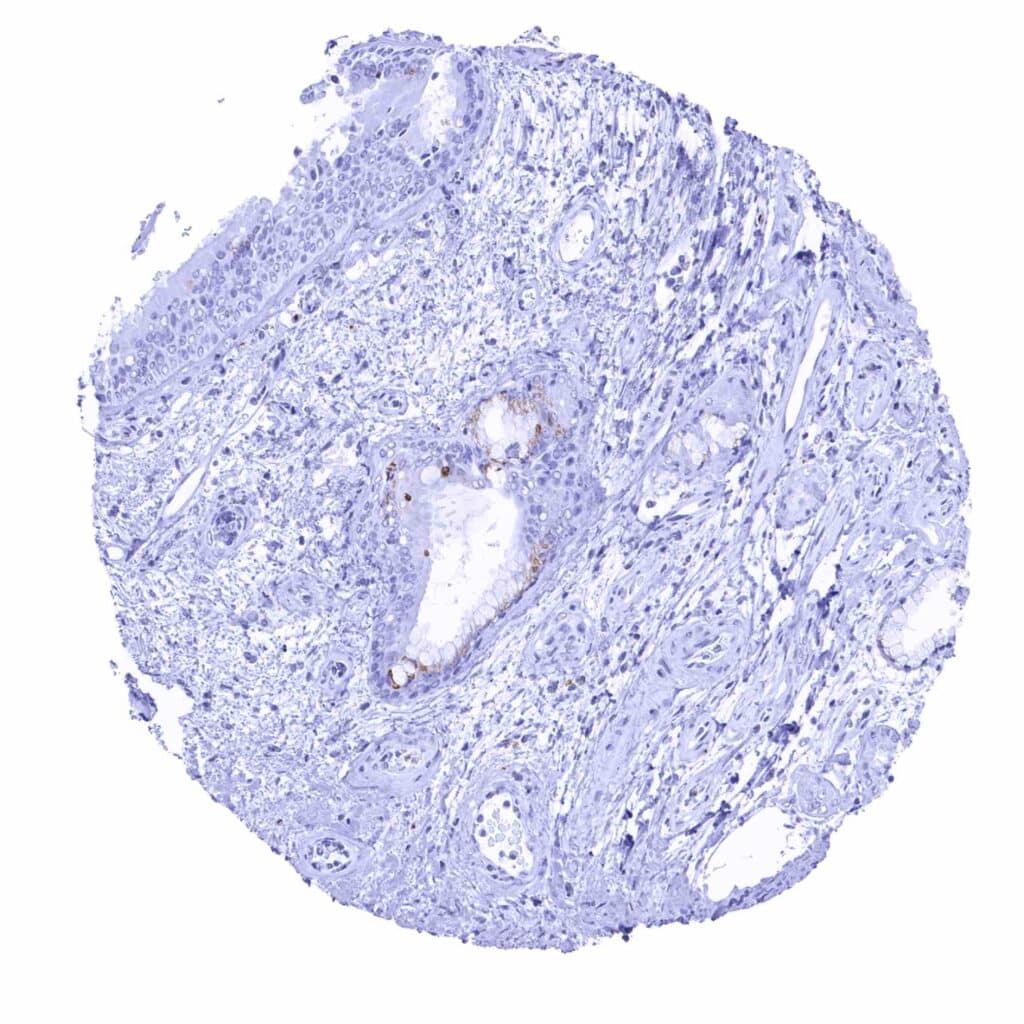

Stomach, antrum – Granular cytoplasmic prostein staining of moderate intensity in surface epithelial cells (prostein immunohistochemistry)

Stomach, corpus – Granular cytoplasmic prostein staining of moderate intensity in surface epithelial cells (prostein immunohistochemistry)